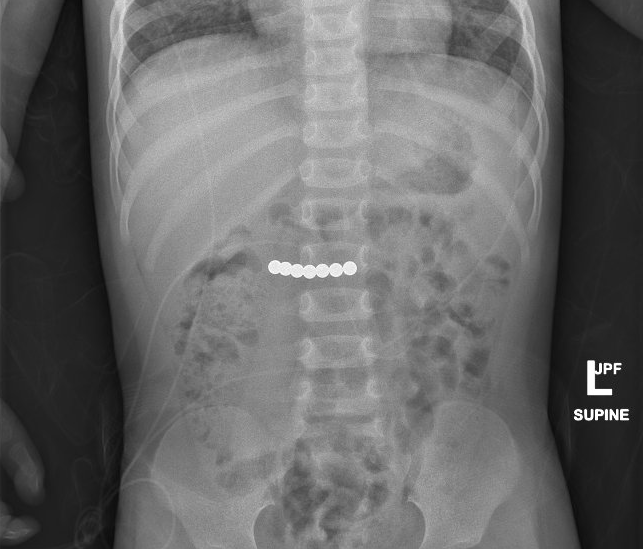

X-ray showing rare earth magnets (the circular white objects) that have been swallowed and have magnetically adhered together within the intestinal tract. When the magnets stick together, they may pinch the child's bowel, which may cause a perforation (hole). That hole can leak stomach acid, food from the intestine, or stool into the abdomen, which can make the child extremely sick. Most magnet ingestions require some sort of surgical intervention.